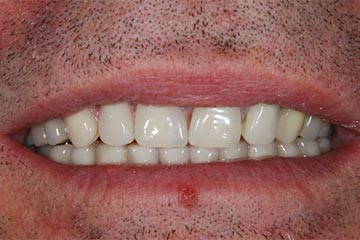

Faccette estetiche in ceramica

Riabilitazione gnatologica, ortodontica ed estetica

Durata del trattamento: un anno